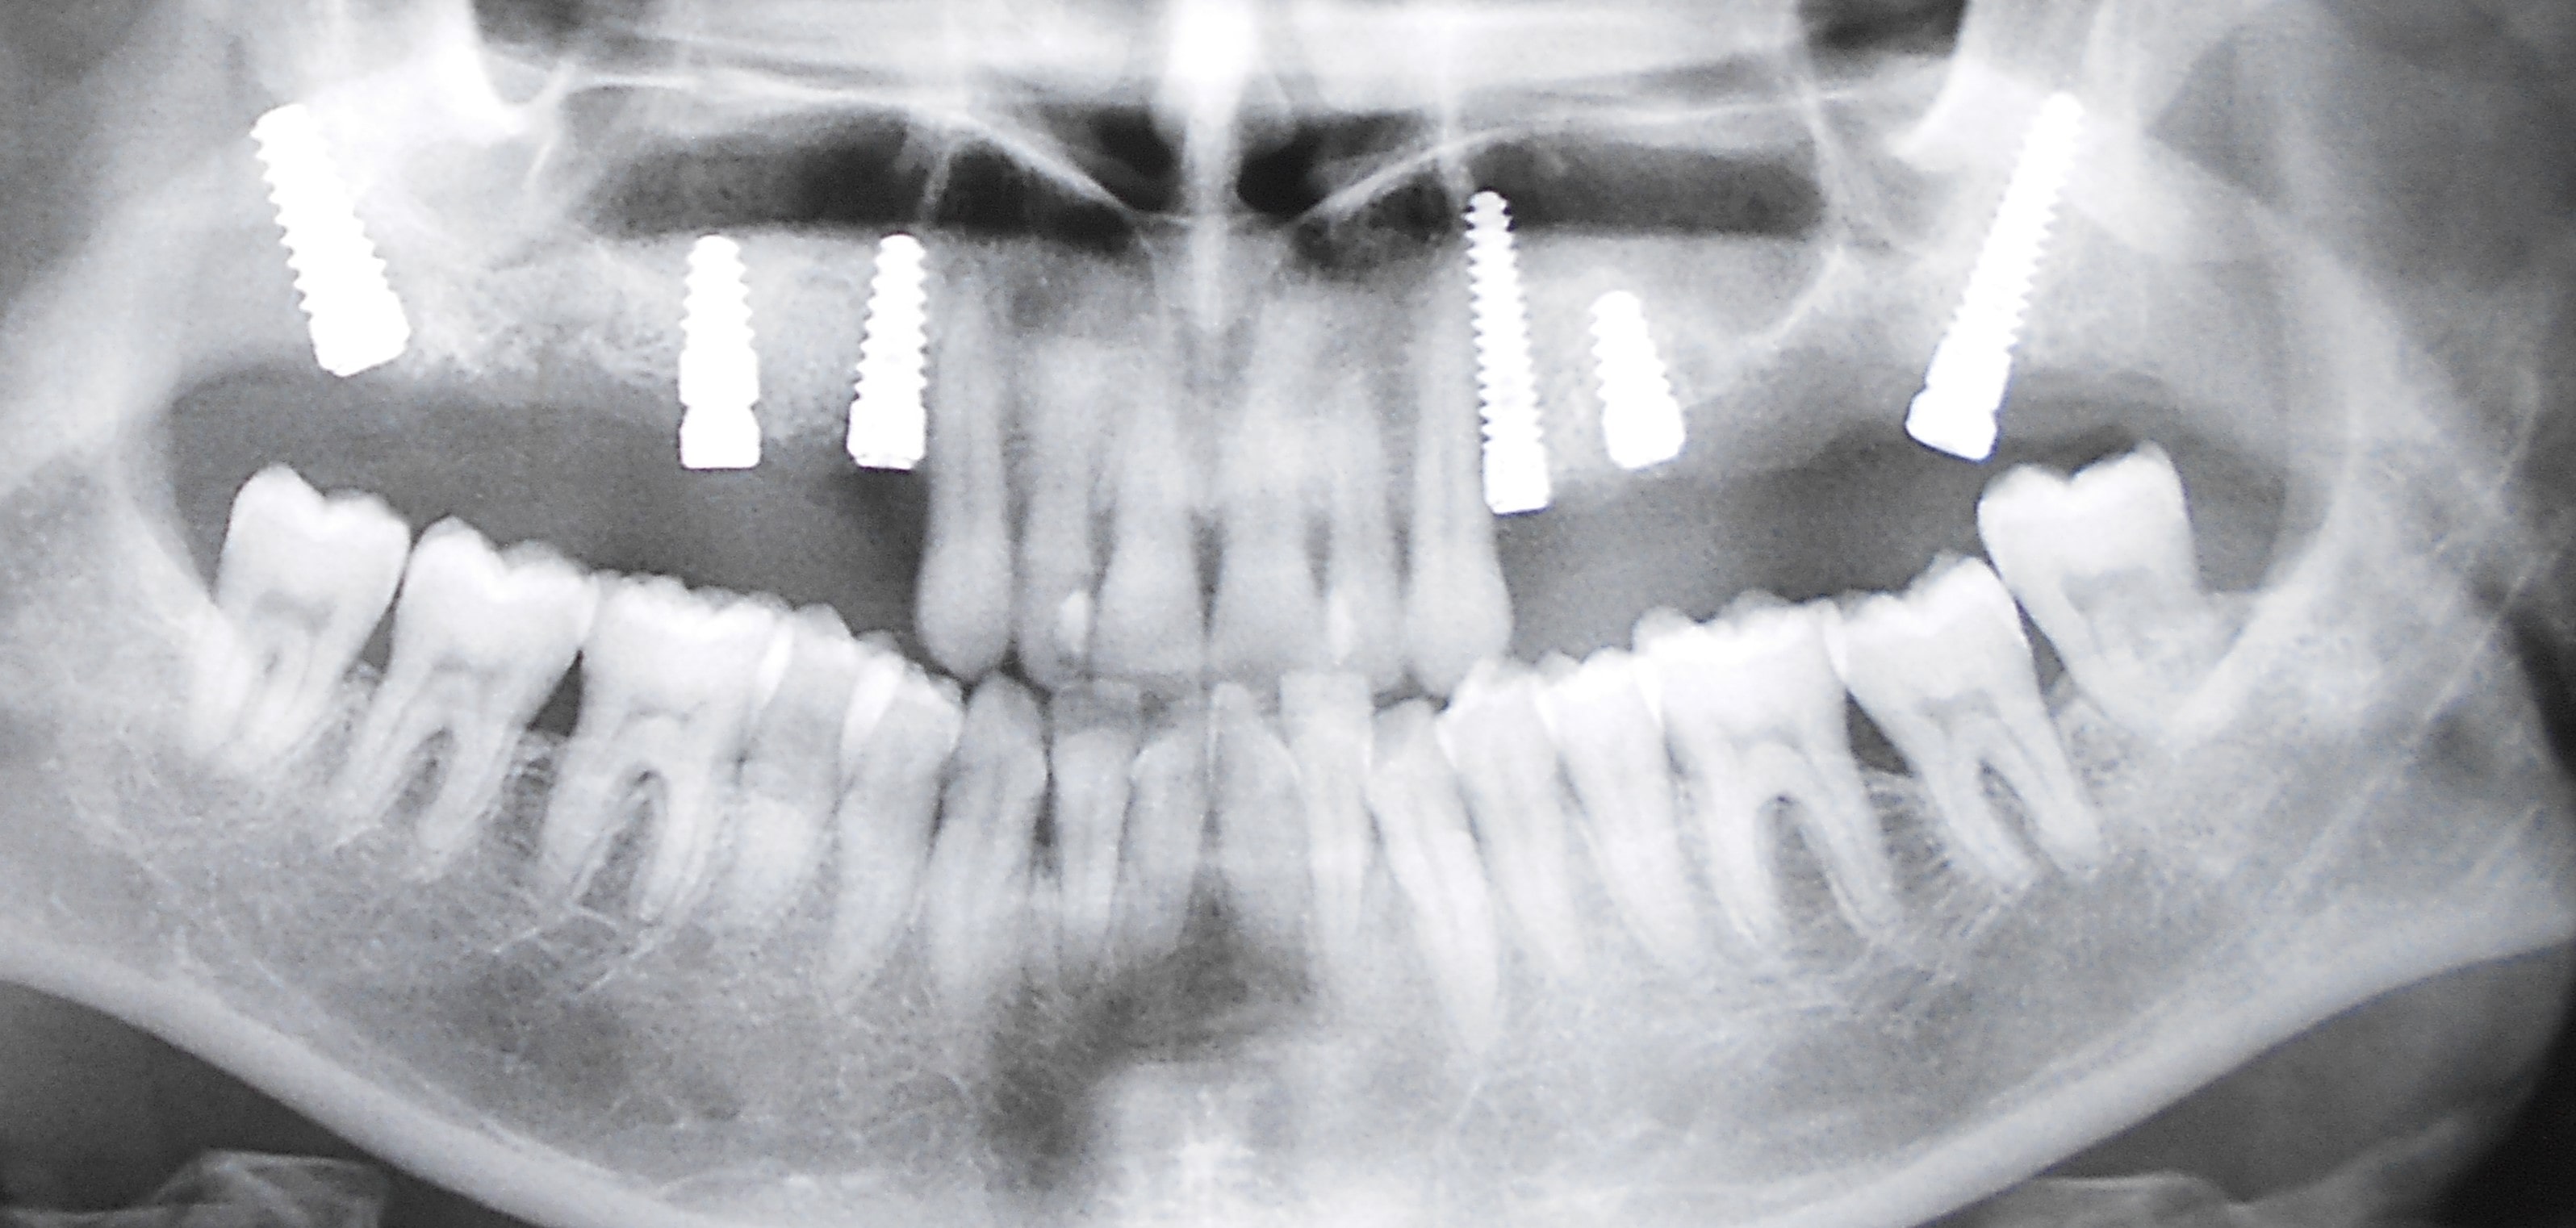

Pacijent dolazi sa starim mostovima i izraženom parodontopatijom u donjoj vilici. Urađeno je skidanje postojećih mostova i istovremena ekstrakcija svih parodontopatičhin zuba uz ugradnju sedam implantata u gornjoj vilici i pet implantata u donjoj vilici. Pacijent je nakon tri dana bio privremneo protetski zbrinut sa fiksnim privremeni krunicama koje su fiksirane na tek ugrađenim implantaima. Nakon četiri meseca je izrađen fiksni cirkonijum kermički- bezmetalni most u gornjoj i donjoj vilici. Rad uspešno završen pre tri godine.